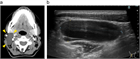

1. 頸部嚢胞性疾患は、先天性と後天性に区分される。先天性疾患は、小児・若年者の疾患であり、発生に沿った局所部位に波動を伴う腫瘤として確認される。これらの病態の理解には発生学の知識が必要になる。また、実際に臨床上の「嚢胞性」のなかに、画像上は充実性にみえる場合(蛋白濃度が高い内容液や血液を含む嚢胞)や、充実性腫瘍(脂肪腫は柔らかいため嚢胞性腫瘤の理学的所見を呈している)も含まれる。ただ、一般的に嚢胞とは分泌物が袋状に貯まる病態を指す( G)。

1. 頭頸部画像診断上、位置、形状、大きさ、壁の性状、境界、隔壁の有無、充実性部分や石灰化の有無、発生部位と進展範囲などが評価される。